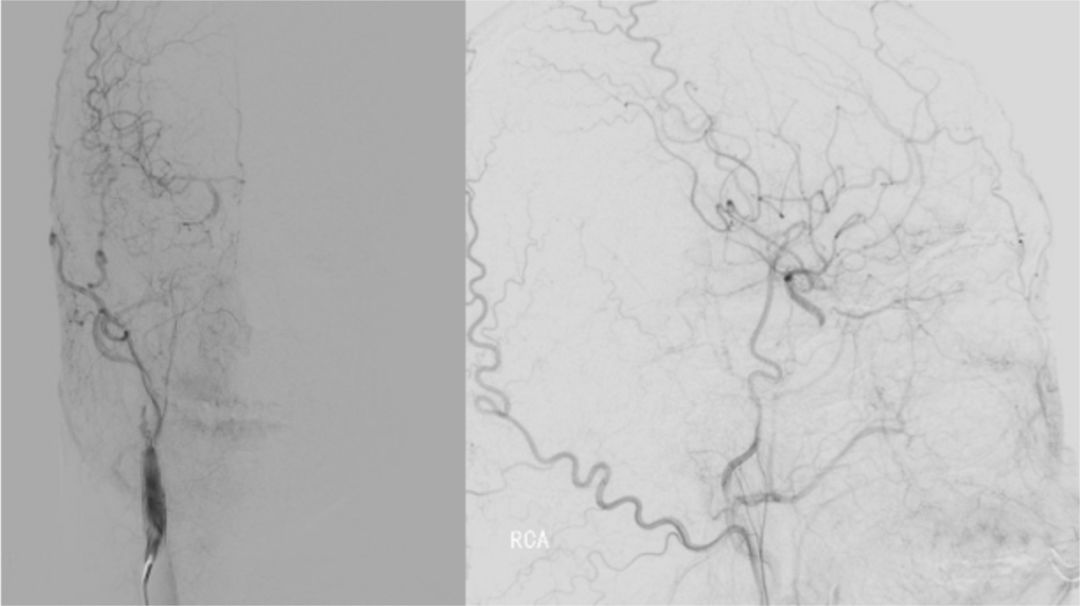

2019-06-07外院DSA:右侧颈内动脉闭塞(图2)。

图2